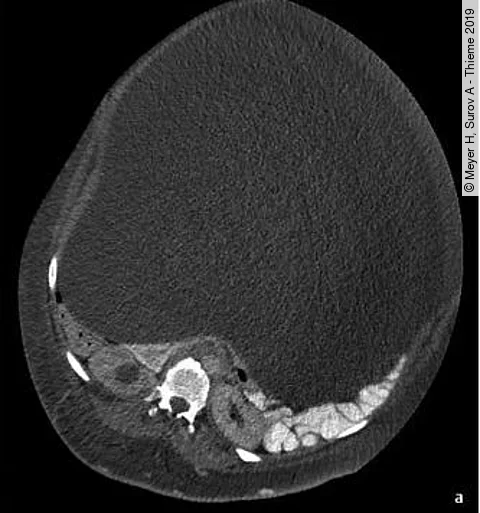

Eine 43-Jährige stellt sich in der Notaufnahme mit einer seit 2 Jahren langsam wachsenden abdominellen Schwellung vor. Sie leidet nur unter milden Bauchschmerzen, die jedoch in den letzten 2 Wochen stärker geworden sind. In der klinischen Untersuchung sah man eine enorme Schwellung des Abdomens. Zur weitergehenden Abklärung erfolgt eine kontrastmittelgestützte Computertomografie des Abdomens.